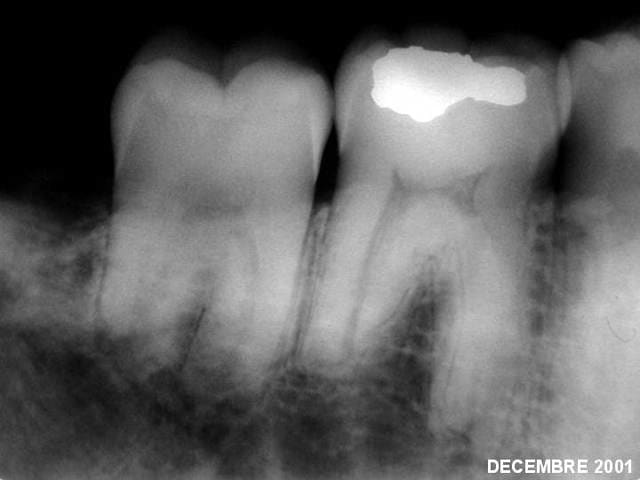

Bon c'est bientôt Noël, et comme j'ai eu la réponse, je vous la fournis en (presque) direct live.

L'argumentaire devrait suivre dans la journée.

Réponse :

Aucun traitement n’était nécessaire.

24 mois plus tard :

. La cicatrisation osseuse est complète;

. Toutes les dents ont retrouvé des sensibilités normales (chaud, froid, percussion)

. Les paresthésies ont disparu.

P.S bravo à athos et guttaman pour leur sagacité. al tu es nul, je le dis publiquement :)

La bonne et unique réponse était l’abstention du moindre geste thérapeutique.

N’oublions jamais les paroles d’Hippocrates : « Primum non nocere ».

L’ablation des améloblastomes était donc largement suffisante dans ce cas précis. C’est la raison pour laquelle il fallait s’abstenir de tout traitement supplémentaire et n’envisager un traitement endodontique sur telle ou telle dent que si, au bout de plusieurs mois, la cicatrisation osseuse n’avait été complète et si les tests de vitalité s’étaient avérés être encore négatifs malgré la disparition des paresthésies.